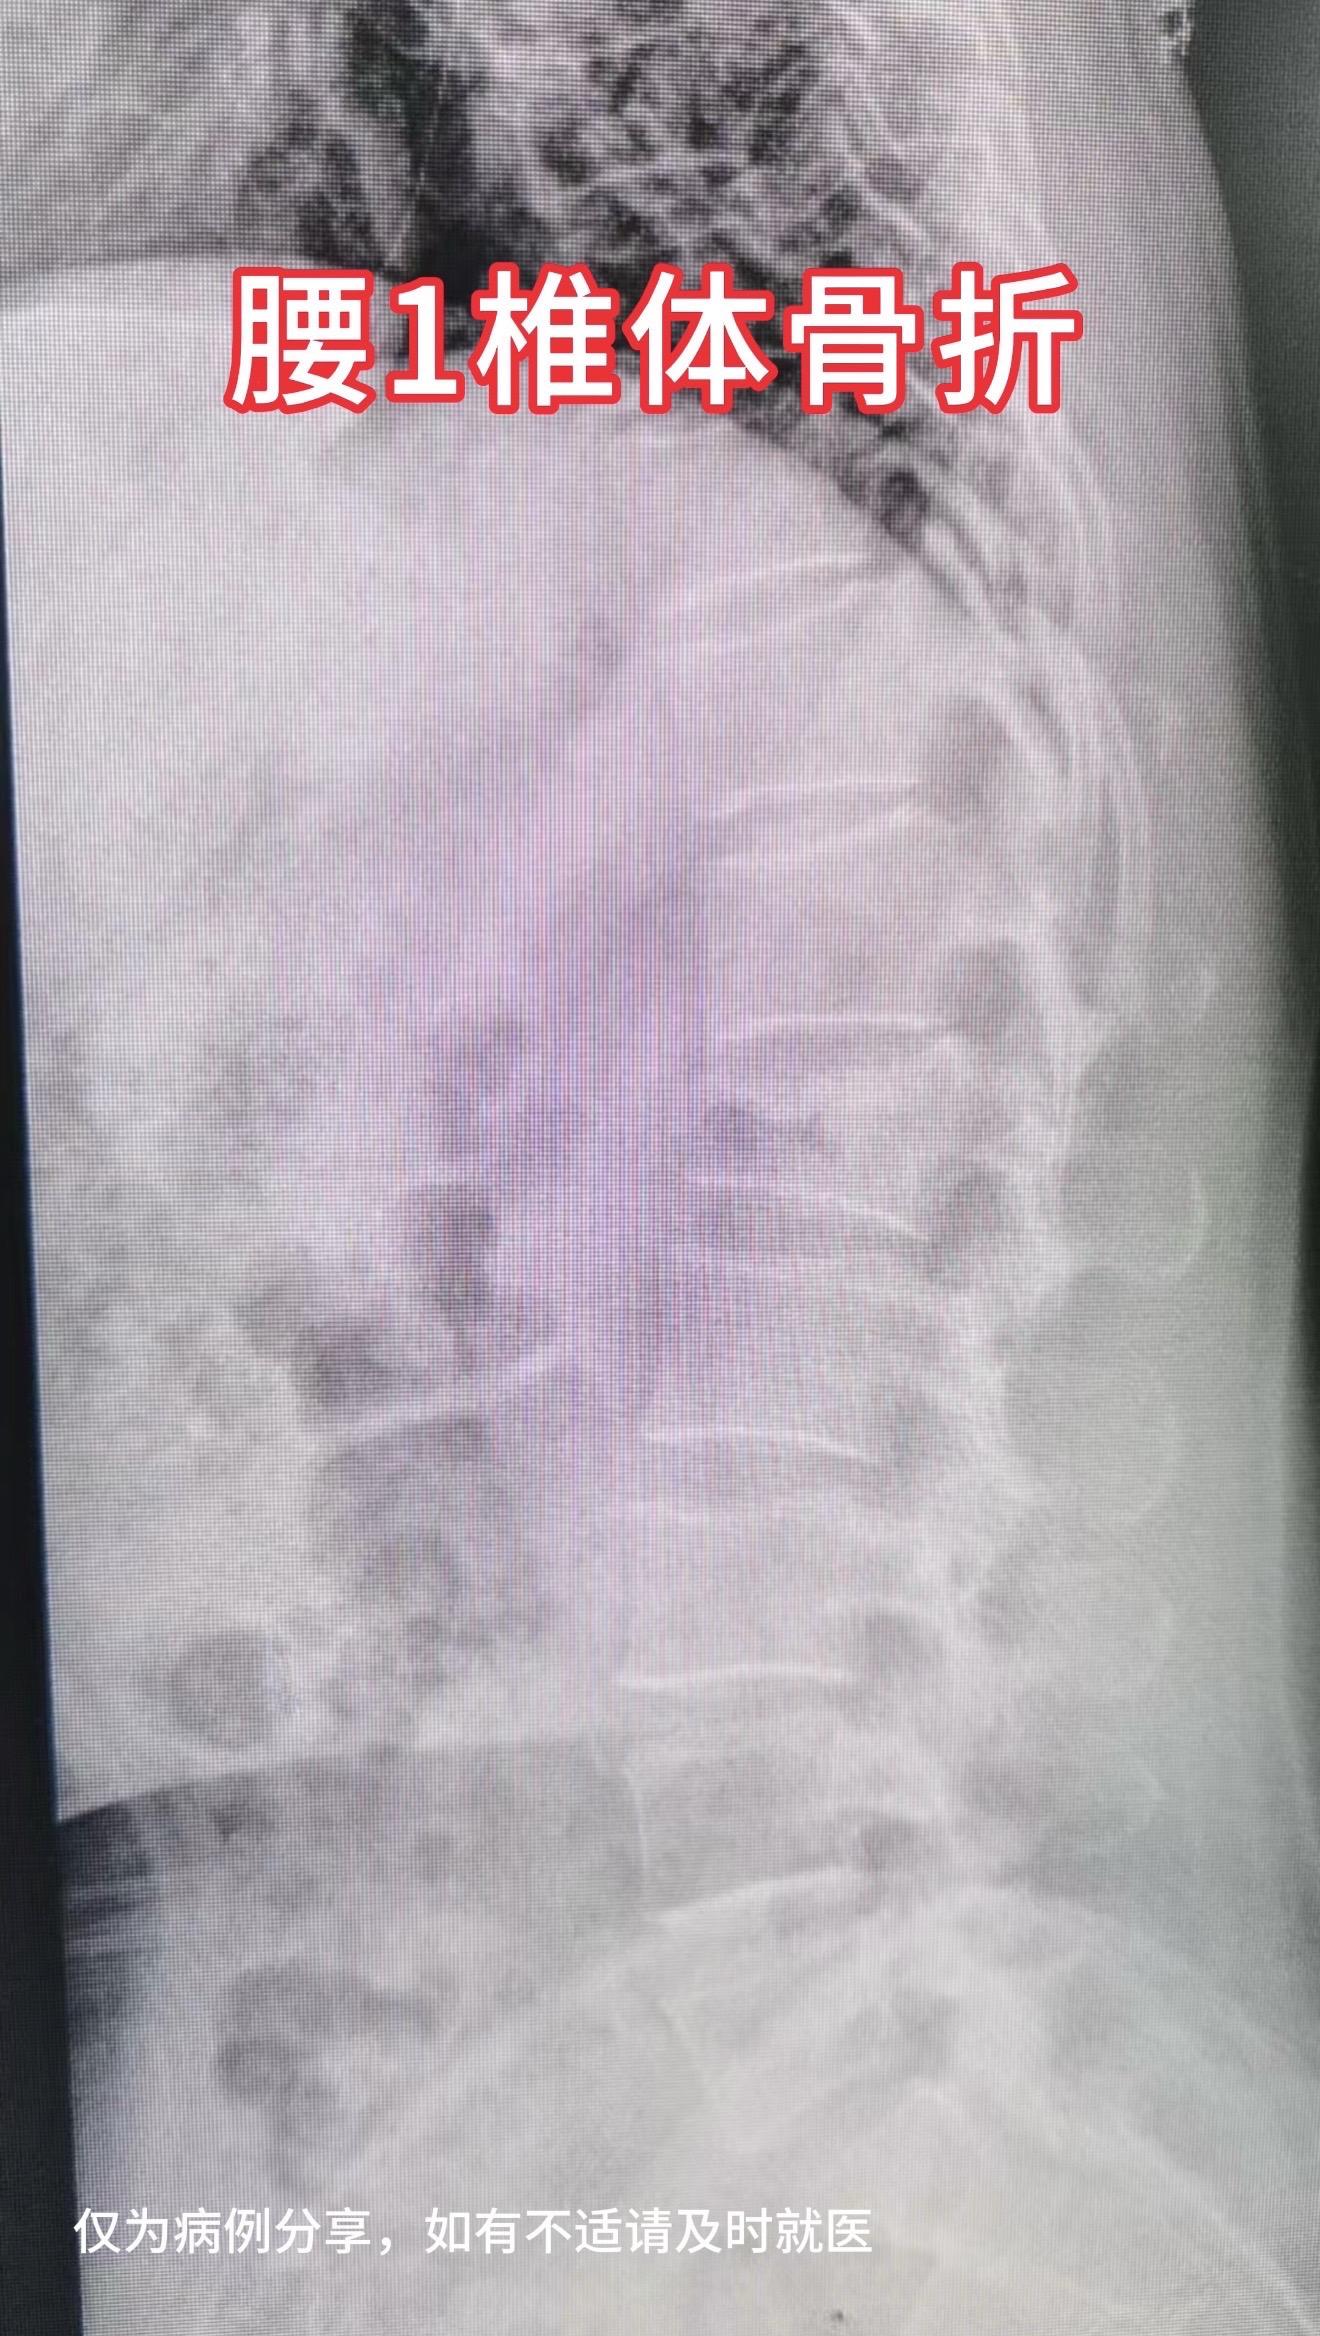

50多岁女性,在家干农活时从凳子上摔下,腰1椎体骨折,手术后复位理想...

50多岁女性,在家干农活时从凳子上摔下,腰1椎体骨折,手术后复位理想,愿患者早日康复